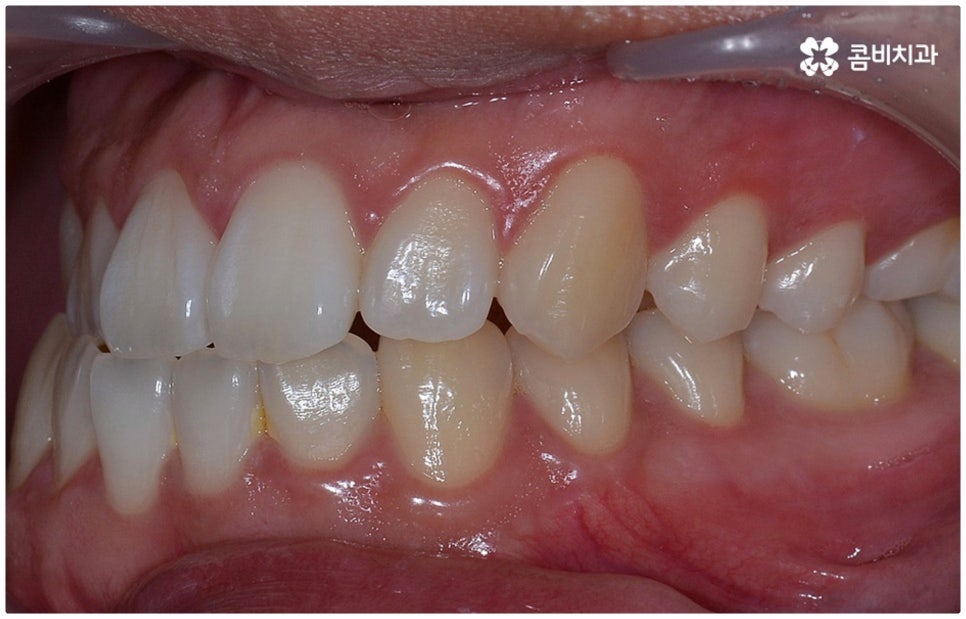

위아래 치아의 교합이 잘 맞지 않는 부정교합을 가지고 있으면 외적인 자신감이 떨어질 뿐 아니라 기능적으로 잘 씹지 못하고 말을 할 때도 발음이 부정확해지는 문제가 생길 수 있기 때문에 교정 치료 등으로 바로잡아 줄 필요가 있어요. 부정교합은 1급, 2급, 3급으로 나눌 수 있는데 오늘은 특히 부정교합 3급 중 절단교합 케이스에 대해 자세하게 알아보려고 하고 있습니다.

부정교합 3급 이란 입을 다물었을 때 아래 어금니가 윗 어금니보다 전방에 위치한 경우를 가리키는 것으로 그 중 절단교합은 이 상태에서 위아래 앞니 끝과 끝이 맞닿는 교합을 의미하는 거예요. 이에 비해 정상적인 교합은 어금니는 똑바로 맞물리고 윗 앞니는 아랫 앞니를 살짝 덮는 정도로 겹쳐지면서 자연스럽게 조금 앞으로 나와 있는 상태를 말하고 있습니다.

이때 심하지 않은 절단교합의 경우 환자분들의 입장에서는 하악이 상악보다 상대적으로 튀어나와 주걱턱처럼 보이는 정도가 그렇게까지 크지는 않다 느끼실 수 있는데요. 특히 또 다른 부정교합 3급 케이스 중 하나인 반대교합 (아래 앞니가 윗 앞니보다 더 앞으로 나가 거꾸로 물리는 경우) 과 비교해 보면 더욱 심각하게 생각되지 않을 수 있어요.

물론 교정 치료에 적기가 정해져 있는 것은 아니기 때문에 성인 이후 중장년 환자분들이라도 교정 치료가 불가능하지는 않으며 상황에 따라 비수술적인 방법으로도 얼마든지 불편함을 줄일 수 있는 경우가 있으니 정확하게 진단한 후 각자에게 맞는 교정 계획을 세워 무리하지 않게 치료를 진행하시길 바라고 있어요. 특히 턱관절과 관련된 부분을 개선하기 위해서는 양악 수술 밖에 방법이 없는 것이 아닌가 생각하셨던 분들이라면 먼저 치과에 내원하셔서 검진과 상담부터 진행해 보시면 마음의 부담을 덜 수 있어 좋을 거예요. 부정교합 3급 치열 (절단교합과 일부 반대교합이 병행되어 있음) 을 가지고 있는 성인분도 교정 치료를 통해 훨씬 자연스럽게 개선이 가능할 수 있으며, 관련 기술 개발 및 미니스크류 등 여러 장치의 발전을 통해 예전에는 적용이 어려웠던 케이스들도 이제는 교정 치료의 도움을 받을 수 있습니다.